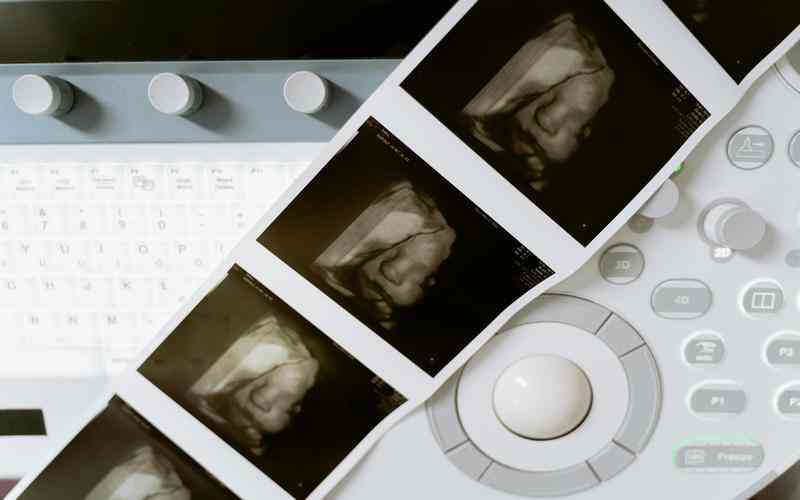

心臟超聲圖像和磁共振成像(MRI)在心血管疾病診斷中的應(yīng)用也日益普及。機(jī)器視覺技術(shù)能夠分析心臟圖像中的心臟功能和結(jié)構(gòu)特征,輔助醫(yī)生識別心肌梗塞、心肌病變等病變情況,為臨床決策提供客觀的數(shù)據(jù)支持。